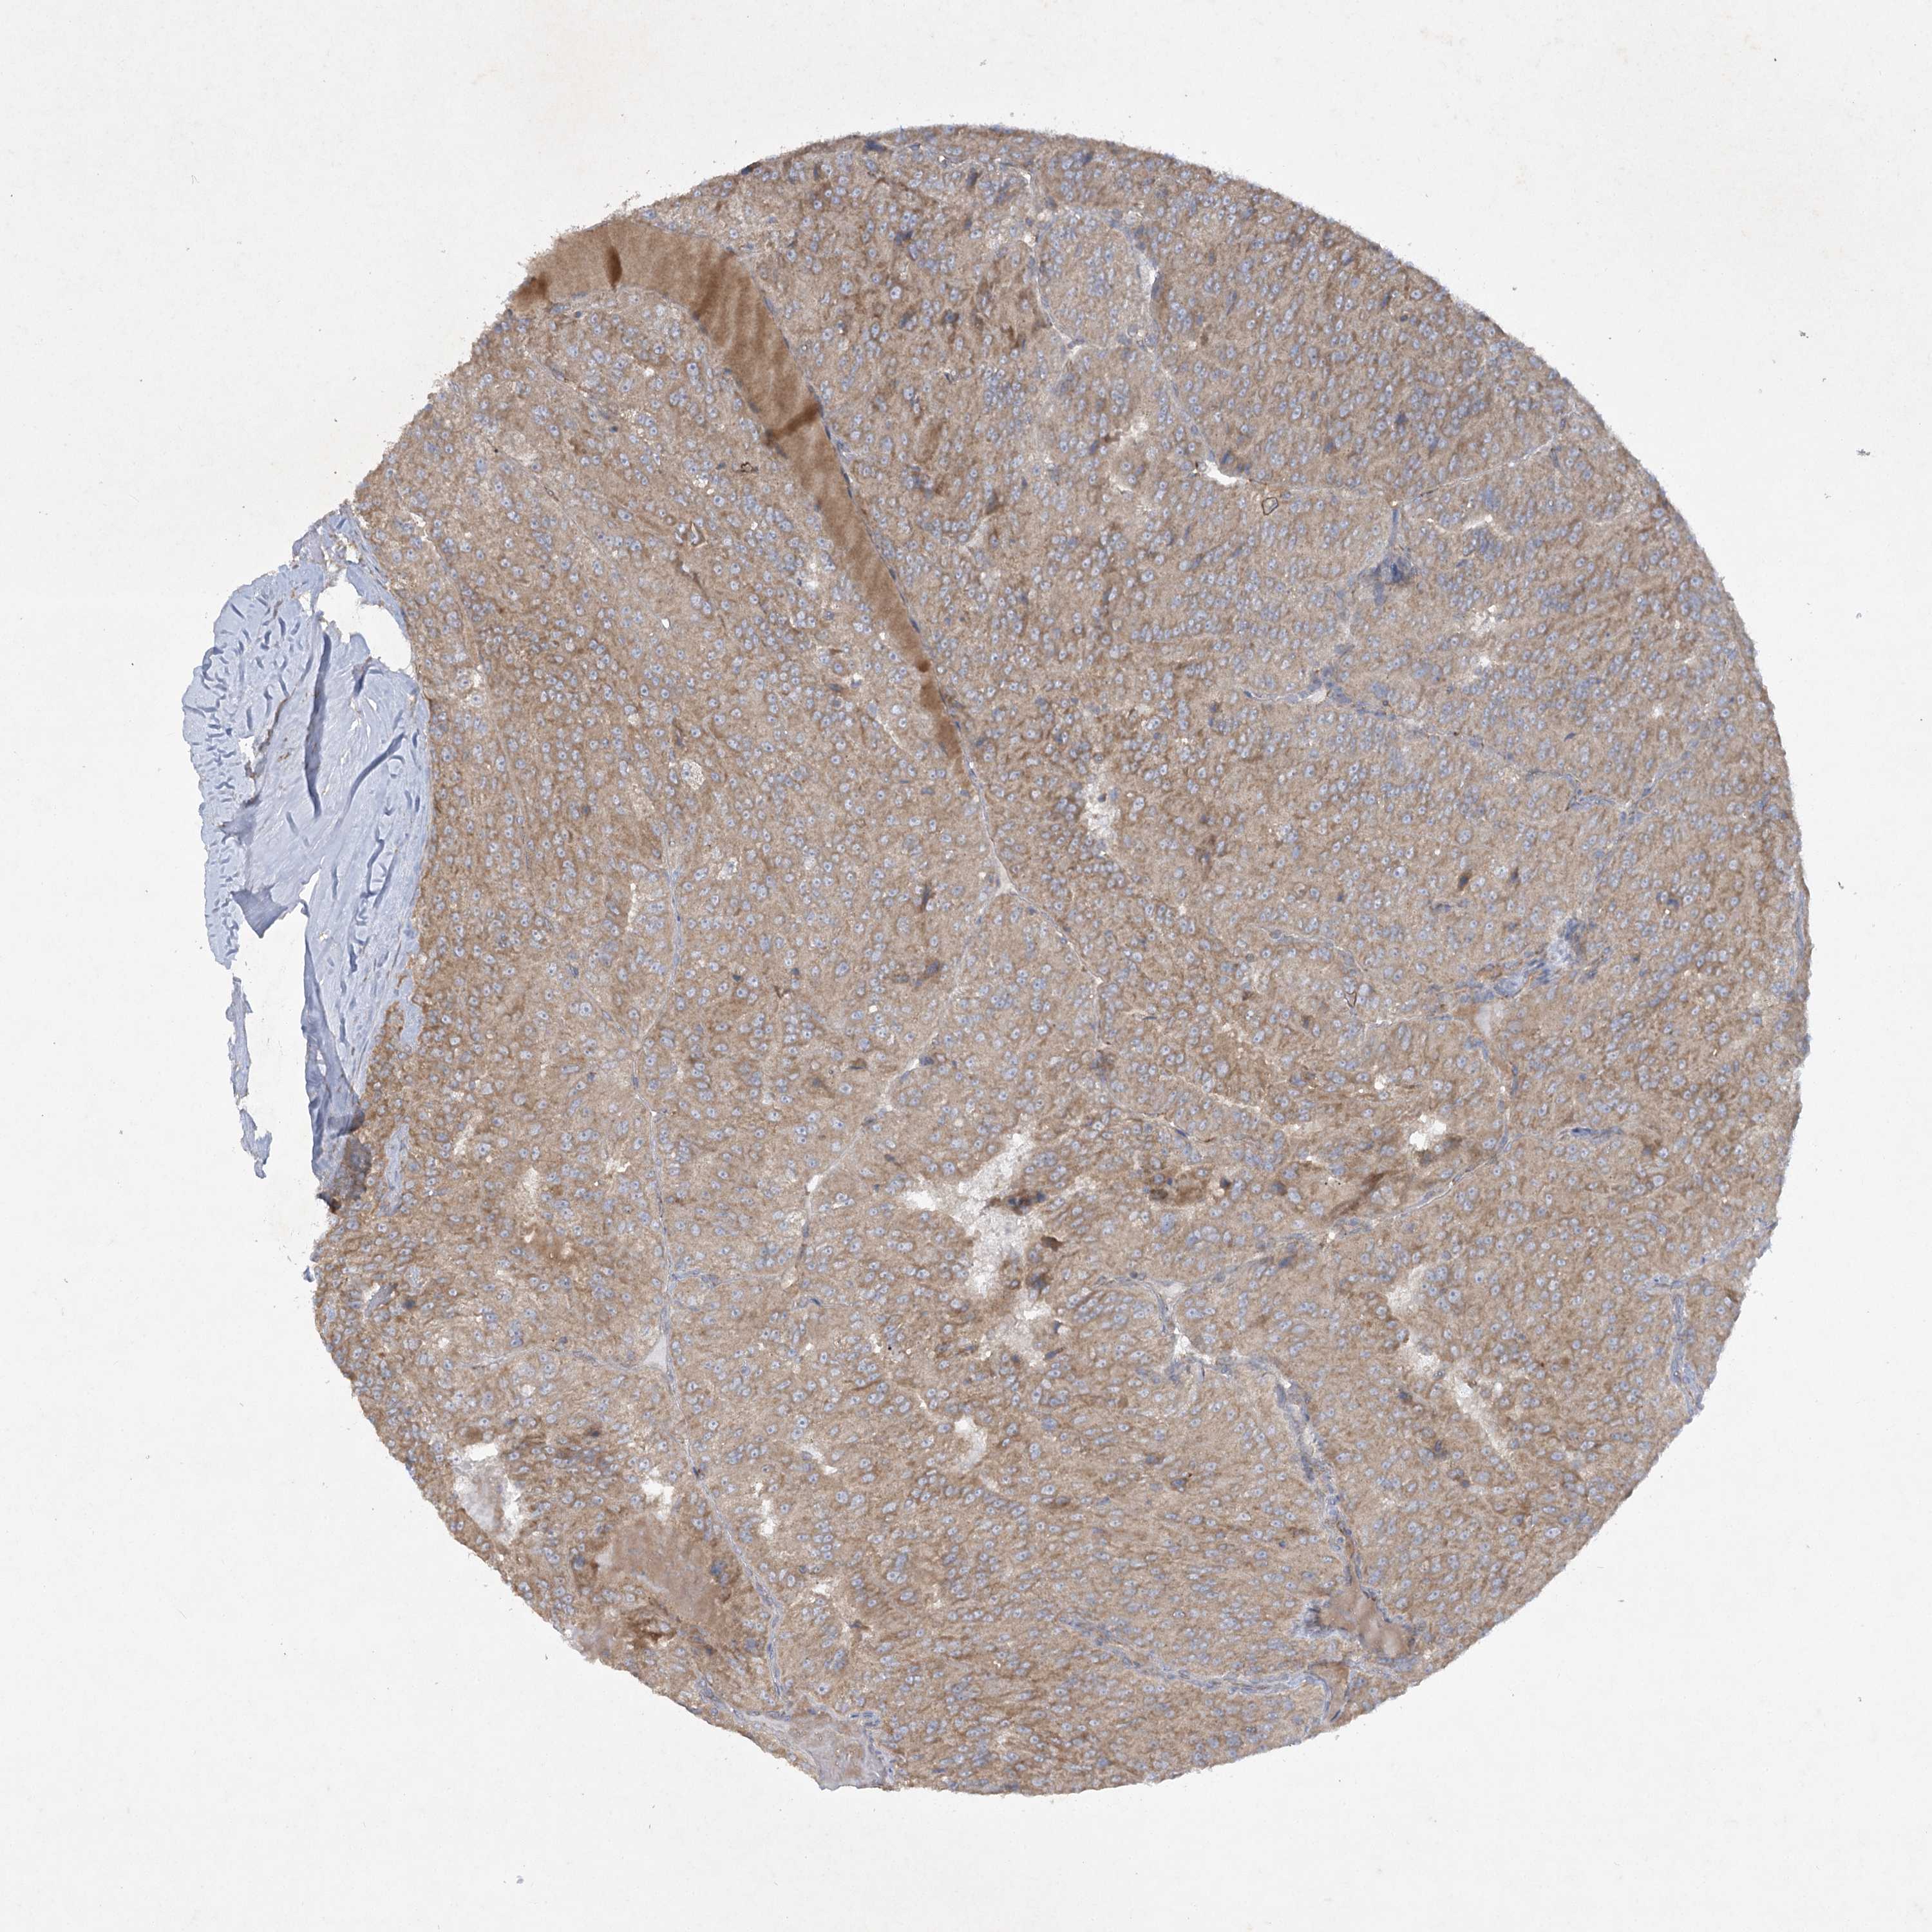

KIDNEY CHROMOPHOBE (TCGA) - Interactive survival scatter ploti

TRAF3IP1 is not prognostic in Kidney Chromophobe (TCGA)

: 4.81

Average pTPM 4.1

Number of samples 64